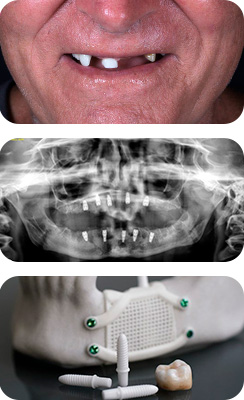

Before diving into the costs, it’s crucial to understand why dental implants are considered a worthwhile investment. Unlike traditional dentures or bridges, dental implants are designed to last a lifetime. This means that, although the initial cost may be higher, the long-term benefits make them a cost-effective solution.

Dental implants offer a natural appearance and a comfortable fit, along with the ability to eat, speak, and smile with confidence. They don’t require adhesives or special care, eliminating additional costs in the long run.

- Number of Implants: The number of implants needed significantly affects the total cost. Single-tooth implants are less expensive than full-mouth restorations.

- Implant Material: Different materials are used for implants, with titanium being the most common. Titanium implants are cost-effective and long-lasting.

- Additional Procedures: Some patients may require additional procedures like bone grafting, which can increase costs.